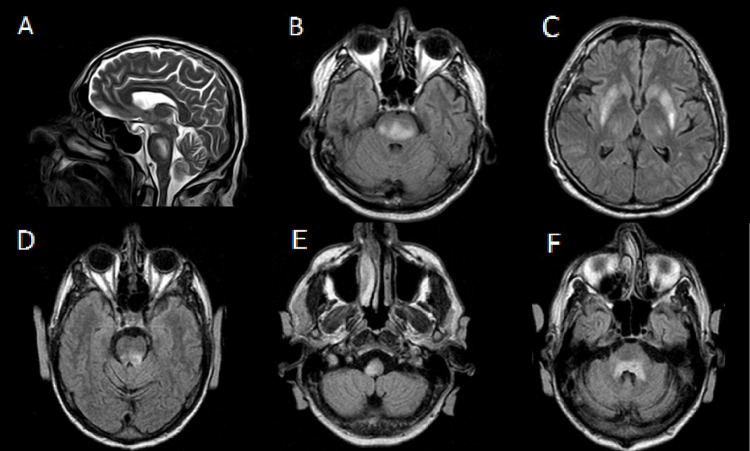

渗透性脱髓鞘综合征(ODS)是一种紧急急性神经系统疾病,通常继发于慢性低钠血症(血液中钠浓度低)的快速纠正。我们报告了两个病例:一个是快速钠校正后的典型ODS,在脑桥和基底节区表现出典型的MRI结果;另一例为非典型ODS,表现为脑神经麻痹和共济失调,尽管钠水平正常,MRI显示脑桥和髓质弥漫性高信号。这些病例强调了ODS的临床和放射学变异性,强调了在高危患者中仔细监测和逐渐纠正电解质(特别是钠)的重要性。

Osmotic demyelination syndrome (ODS) is an emergency acute neurological condition that usually occurs secondary to rapid correction of chronic hyponatremia (low concentration of sodium in the blood). We present two cases: one with typical ODS following rapid sodium correction, showing classic MRI findings in the pons and basal ganglia; and another with atypical ODS presenting with cranial nerve palsy and ataxia, despite normal sodium levels, and diffuse hyperintensities in the pons and medulla on MRI. These cases emphasize the clinical and radiological variability of ODS, highlighting the importance of careful monitoring and gradual correction of electrolytes, particularly sodium, in high-risk patients.